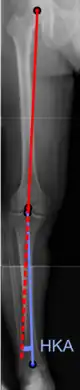

Radiography

On projectional radiography, the degree of varus or valgus deformity can be quantified by the hip-knee-ankle angle,[7] which is an angle between the femoral mechanical axis and the center of the ankle joint.[8] It is normally between 1.0° and 1.5° of varus in adults.[9] Normal ranges are different in children.[10]